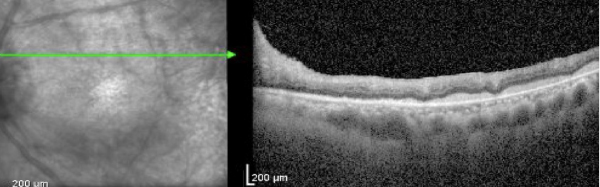

This case report discusses a patient with a history of DLBCL who presented with progressive optic neuropathy despite negative neuro-imaging and cerebrospinal fluid analysis. The case illustrates the limitations of standard CNS surveillance in detecting occult infiltration and highlights the necessity of tissue biopsy for definitive diagnosis.